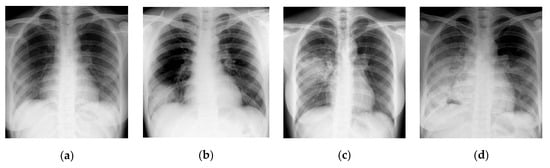

In this section, CT scans of the human chest are analyzed using a GLCM-based texture analysis approach. GLCM is a popular texture classification approach with which texture quantification of the image data is performed. GLCM offers information regarding the “spectral” and “spatial” variation in the image pixels. A time series of four CT scans of the lung chamber of a human chest infected with the COVID-19 virus is shown in Figure 18. These images are obtained from the “Italian Society of Radiology” [86]. Texture quantification of these images is performed to identify the pattern of change that developed in the visual statistical features due to the severity of the virus.

Figure 18.

Time series of CT scans of a human chest infected from COVID-19 virus (a) Day 1 (b) Day 7 (c) Day 14 (d) Day 21 [86].

Figure 18 presents the time series representation of the patient’s chest. Figure 18a illustrates the earliest image of the chest infected with the COVID-19 virus. At the same time, Figure 18b–d shows the decrease in infection in the human chest in descending order. Finally, Figure 18d illustrates the least amount of infection in the human chest. These images are converted into HSV image format to visually represent the change developed in the human chest over time. Texture quantification of the image can be performed using the GLCM technique. The GLCM calculation from an input image can be understood by reviewing Figure 19.